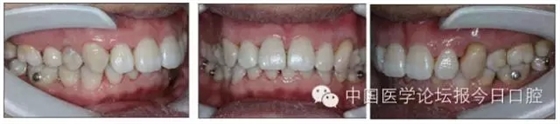

本病例為慢性牙周炎致前牙漂移、深覆(牙合)患者。本病例采用無托槽隱形矯治技術進行治療。無托槽隱形矯治器具有可摘戴、便于口腔衛(wèi)生維護和牙周治療的優(yōu)點,更適合于伴有牙周炎的錯(牙合)畸形患者的治療。 患者男,48歲,前牙有縫、前突求診。 患者面部對稱,側(cè)面觀上頜前突,下頜后縮。 口內(nèi)情況:恒牙列,24、34、44缺失,磨牙Ⅲ類關系,上牙列散隙,上前牙扇形漂移。前牙深覆(牙合)、深覆蓋??谇恍l(wèi)生較差,11與12間牙齦乳頭紅腫,多個牙探診有牙周袋形成,11松動Ⅰ度,余切牙松動(-),患者面像及口內(nèi)像如圖1、2所示。 圖1 治療前面像 圖2 治療前口內(nèi)像 全口曲面體層片(圖3)顯示,患者全牙列牙槽骨吸收;根尖片(圖4)示11近中牙槽骨角形吸收已達根尖1/3,21牙槽骨嵴頂吸收至根1/2,23牙槽骨近中骨板角形吸收至根1/2。磨牙區(qū)骨嵴頂吸收3mm。治療前頭顱側(cè)位片見圖3,治療前ODS模型見圖5。 圖4 治療前根尖片 圖5 治療前ODS模型 牙型:安氏Ⅲ類。骨型:Ⅱ類。面型:上頜前突,下頜后縮。 問題列表為:①上牙列間隙;②上切牙病理性牙移位;③前牙深覆(牙合)、深覆蓋;④24、34、44缺失;⑤慢性牙周炎。 矯治目標包括:①排齊牙列,關閉牙列間隙;②改善前牙深覆(牙合)、深覆蓋;③改善牙周狀況。 矯治設計有:①牙周基礎治療與維護。②壓低、內(nèi)收上切牙,關閉上牙列間隙。③壓低下切牙,伸長下后牙,整平Spee曲線,改善前牙覆(牙合)、覆蓋。 患者進行全口齦上潔治、齦下刮治,口腔衛(wèi)生宣教,并按牙周醫(yī)師的要求,每2~3個月行牙周檢查與治療。 牙周基礎治療結(jié)束3個月,開始隱形矯治。于14、25、35、36、45、46上粘接附件(圖6),于16、26(牙合)面粘接(牙合)墊。 圖6 ODS設計附件粘接圖示 矯治過程中注意(牙合)墊是否脫落或磨損,及時修補。 注意上前牙內(nèi)收時有無咬合干擾,及時調(diào)(牙合)。下頜前磨牙伸長到位后,磨除16、26(牙合)墊。 下頜佩戴第24步矯治器時,分別在36、37、46、47的頰、舌側(cè)粘接舌扣,矯治器上預留伸長空間,用3/16英寸、3.5盎司皮圈牽引,輔助伸長下磨牙(圖7)。 患者共戴用矯治器上頜32步,下頜26步。 矯治后,牙列間隙關閉,面型及覆(牙合)覆蓋改善。11根尖片(圖8)顯示,治療后較治療前,牙周支持組織增加,牙槽骨角形吸收區(qū)水平向縮小0.3mm,垂直向縮小0.6mm。11松動Ⅰ度,余切牙無松動。 圖8 治療后根尖片 圖9 治療后口內(nèi)像 圖10 治療后X線檢查 圖11 治療后ODS模型 正畸-牙周聯(lián)合治療對于牙周組織的影響 多學科綜合治療牙周炎患者不再是正畸治療的禁忌證。良好的牙周治療為正畸治療中的牙齒移動打下堅實基礎,而正畸治療排齊牙齒、去除(牙合)干擾,有利于牙周健康。 牙周炎患者的正畸治療必須在牙周炎癥得到控制后才能進行,否則,菌斑會隨著牙齒的移動,特別是壓低而使牙周炎癥加重。牙周炎的正確診斷、牙周炎癥控制、正畸治療中和治療后的認真維護是治療成功的關鍵。根據(jù)臨床需要,一般每2~4周做一次潔治,每3個月進行牙周評估,同時患者必須進行非常良好的日??谇恍l(wèi)生維護。 固定矯治器使得牙周檢查、潔治和日??谇恍l(wèi)生維護變得困難,隱形矯治器可自行摘戴,便于患者日常維護和牙周治療,節(jié)約時間,提高菌斑控制效果。 有臨床研究表明,對于存在(牙合)創(chuàng)傷,伴有角形吸收的患牙,經(jīng)過牙周翻瓣手術控制住牙周炎癥后,使用正畸輕力壓低患牙,可以改善牙槽骨吸收的程度,并獲得一定程度的牙周新附著。本病例切牙壓低后,原來的牙槽骨吸收有改善。 病理性牙移位 病理性牙移位(PTM)在重度牙周炎患者中的發(fā)生率為30%~50%,且常見于上前牙區(qū)。其主要由于牙周支持組織喪失尤其是骨組織的丟失,咬合因素(如后牙缺失、前牙深覆牙合、牙合創(chuàng)傷等),頰舌唇肌力量不平衡及牙周和根尖周組織炎癥所致,是牙周炎患者要求正畸治療的主要原因之一。 PTM須通過正畸、牙周聯(lián)合,有時須配合修復才能達到理想的治療效果。正畸治療通常是壓低牙齒,臨床研究表明,牙周手術配合正畸壓低可以產(chǎn)生新附著,有利于PTM牙周組織的恢復。 本病例右上中切牙牙槽骨角形吸收,在盡量保證治療前后根尖片投照角度一致的情況下,以鄰牙作為校準,在根尖片上對治療前后的骨量進行評價,治療后牙槽骨角形吸收區(qū)水平向縮小0.3 mm,垂直向縮小0.6mm。盡管根尖片并不能說明骨量改變,但從影像學上能看到骨吸收區(qū)域有所減小。 無托槽隱形矯治器矯治牙周病的優(yōu)勢 無托槽隱形矯治器具有可摘戴、便于口腔衛(wèi)生維護和牙周治療的優(yōu)點,更適合于伴有牙周炎的錯(牙合)患者的治療;同時,無托槽隱形矯治器佩戴后具有牙弓夾板和(牙合)板的作用,可有效減少側(cè)向力,有利于牙周的恢復和減輕牙齒松動;由于無托槽隱形矯治器的設計是在三維數(shù)字模型上進行的,每個矯治器移動牙齒的數(shù)量和每個牙齒的移動距離可以得到量化控制,因而可以根據(jù)患者牙槽骨水平和對矯治力的耐受情況個性化設計矯治力,并且可以根據(jù)矯治中牙齒移動情況調(diào)整后續(xù)矯治器的設計。 有關磨牙伸長 單純使用無托槽隱形矯治器同步伸長后牙比較困難。該病例先使用磨牙(牙合)墊打開咬合,通過矯治器伸長前磨牙,在前磨牙建立咬合后,磨除磨牙上的(牙合)墊,通過輔助牽引伸長磨牙,最終達到伸長后牙、整平Spee曲線的目的。 史真,主任醫(yī)師,現(xiàn)任北京黃寺整形外科醫(yī)院口腔科主任,第四軍醫(yī)大學口腔正畸學碩士,為世界正畸醫(yī)師聯(lián)盟(WFO)會員、全軍口腔醫(yī)學專業(yè)委員會委員、中華口腔正畸專業(yè)委員會委員、中華醫(yī)學美學與美容學會齒科美容學組成員、北京口腔醫(yī)學會兒童口腔專業(yè)委員會常務委員、北京口腔醫(yī)學會正畸專業(yè)委員會委員、《中華醫(yī)學美學與美容》雜志審稿專家,是我國最早開展無托槽隱形矯治技術的口腔醫(yī)師之一。